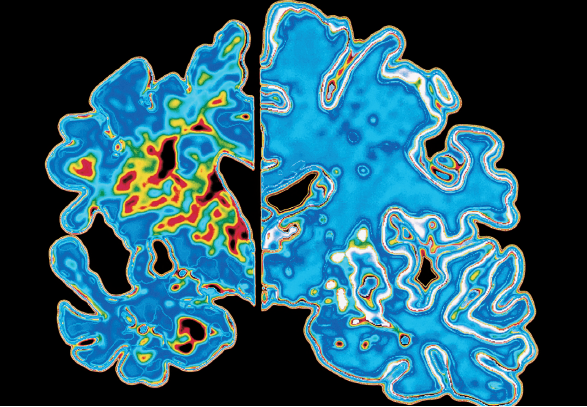

△阿爾茨海默病患者萎縮的大腦切片(左)和正常人的大腦切片(右)